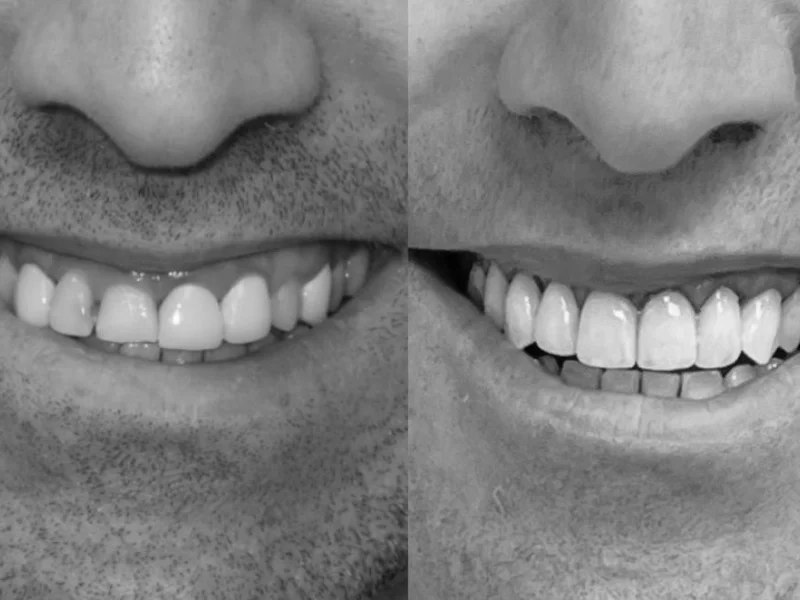

Esthetische tandheelkunde bij Tandartspraktijk Top Lach in Utrecht: facings (porselein en composiet), professioneel tanden bleken (in-office en thuisbleken), composiet restauraties en volkeramische kronen. Van één verkleuring tot een volledige Smile Design make-over — onze tandartsen combineren functionaliteit met een natuurlijk mooi resultaat.

Bij Tandartspraktijk Top Lach geloven wij dat een mooie glimlach niet alleen een kwestie van esthetiek is — het draagt bij aan uw zelfvertrouwen en welzijn. Onze esthetische behandelingen omvatten porselein facings, composiet bonding, professioneel tanden bleken en volkeramische kronen. Elke behandeling wordt zorgvuldig afgestemd op uw natuurlijke tandkleur, vorm en gezichtsverhoudingen.

Tanden bleken is onze meest gevraagde esthetische behandeling. Wij bieden zowel in-office bleken (in de praktijk, direct resultaat) als thuisbleken met op maat gemaakte kappen en professionele bleekgel. Voor een volledig esthetisch traject werken wij met Digital Smile Design — u ziet uw nieuwe glimlach op scherm vóór de behandeling.